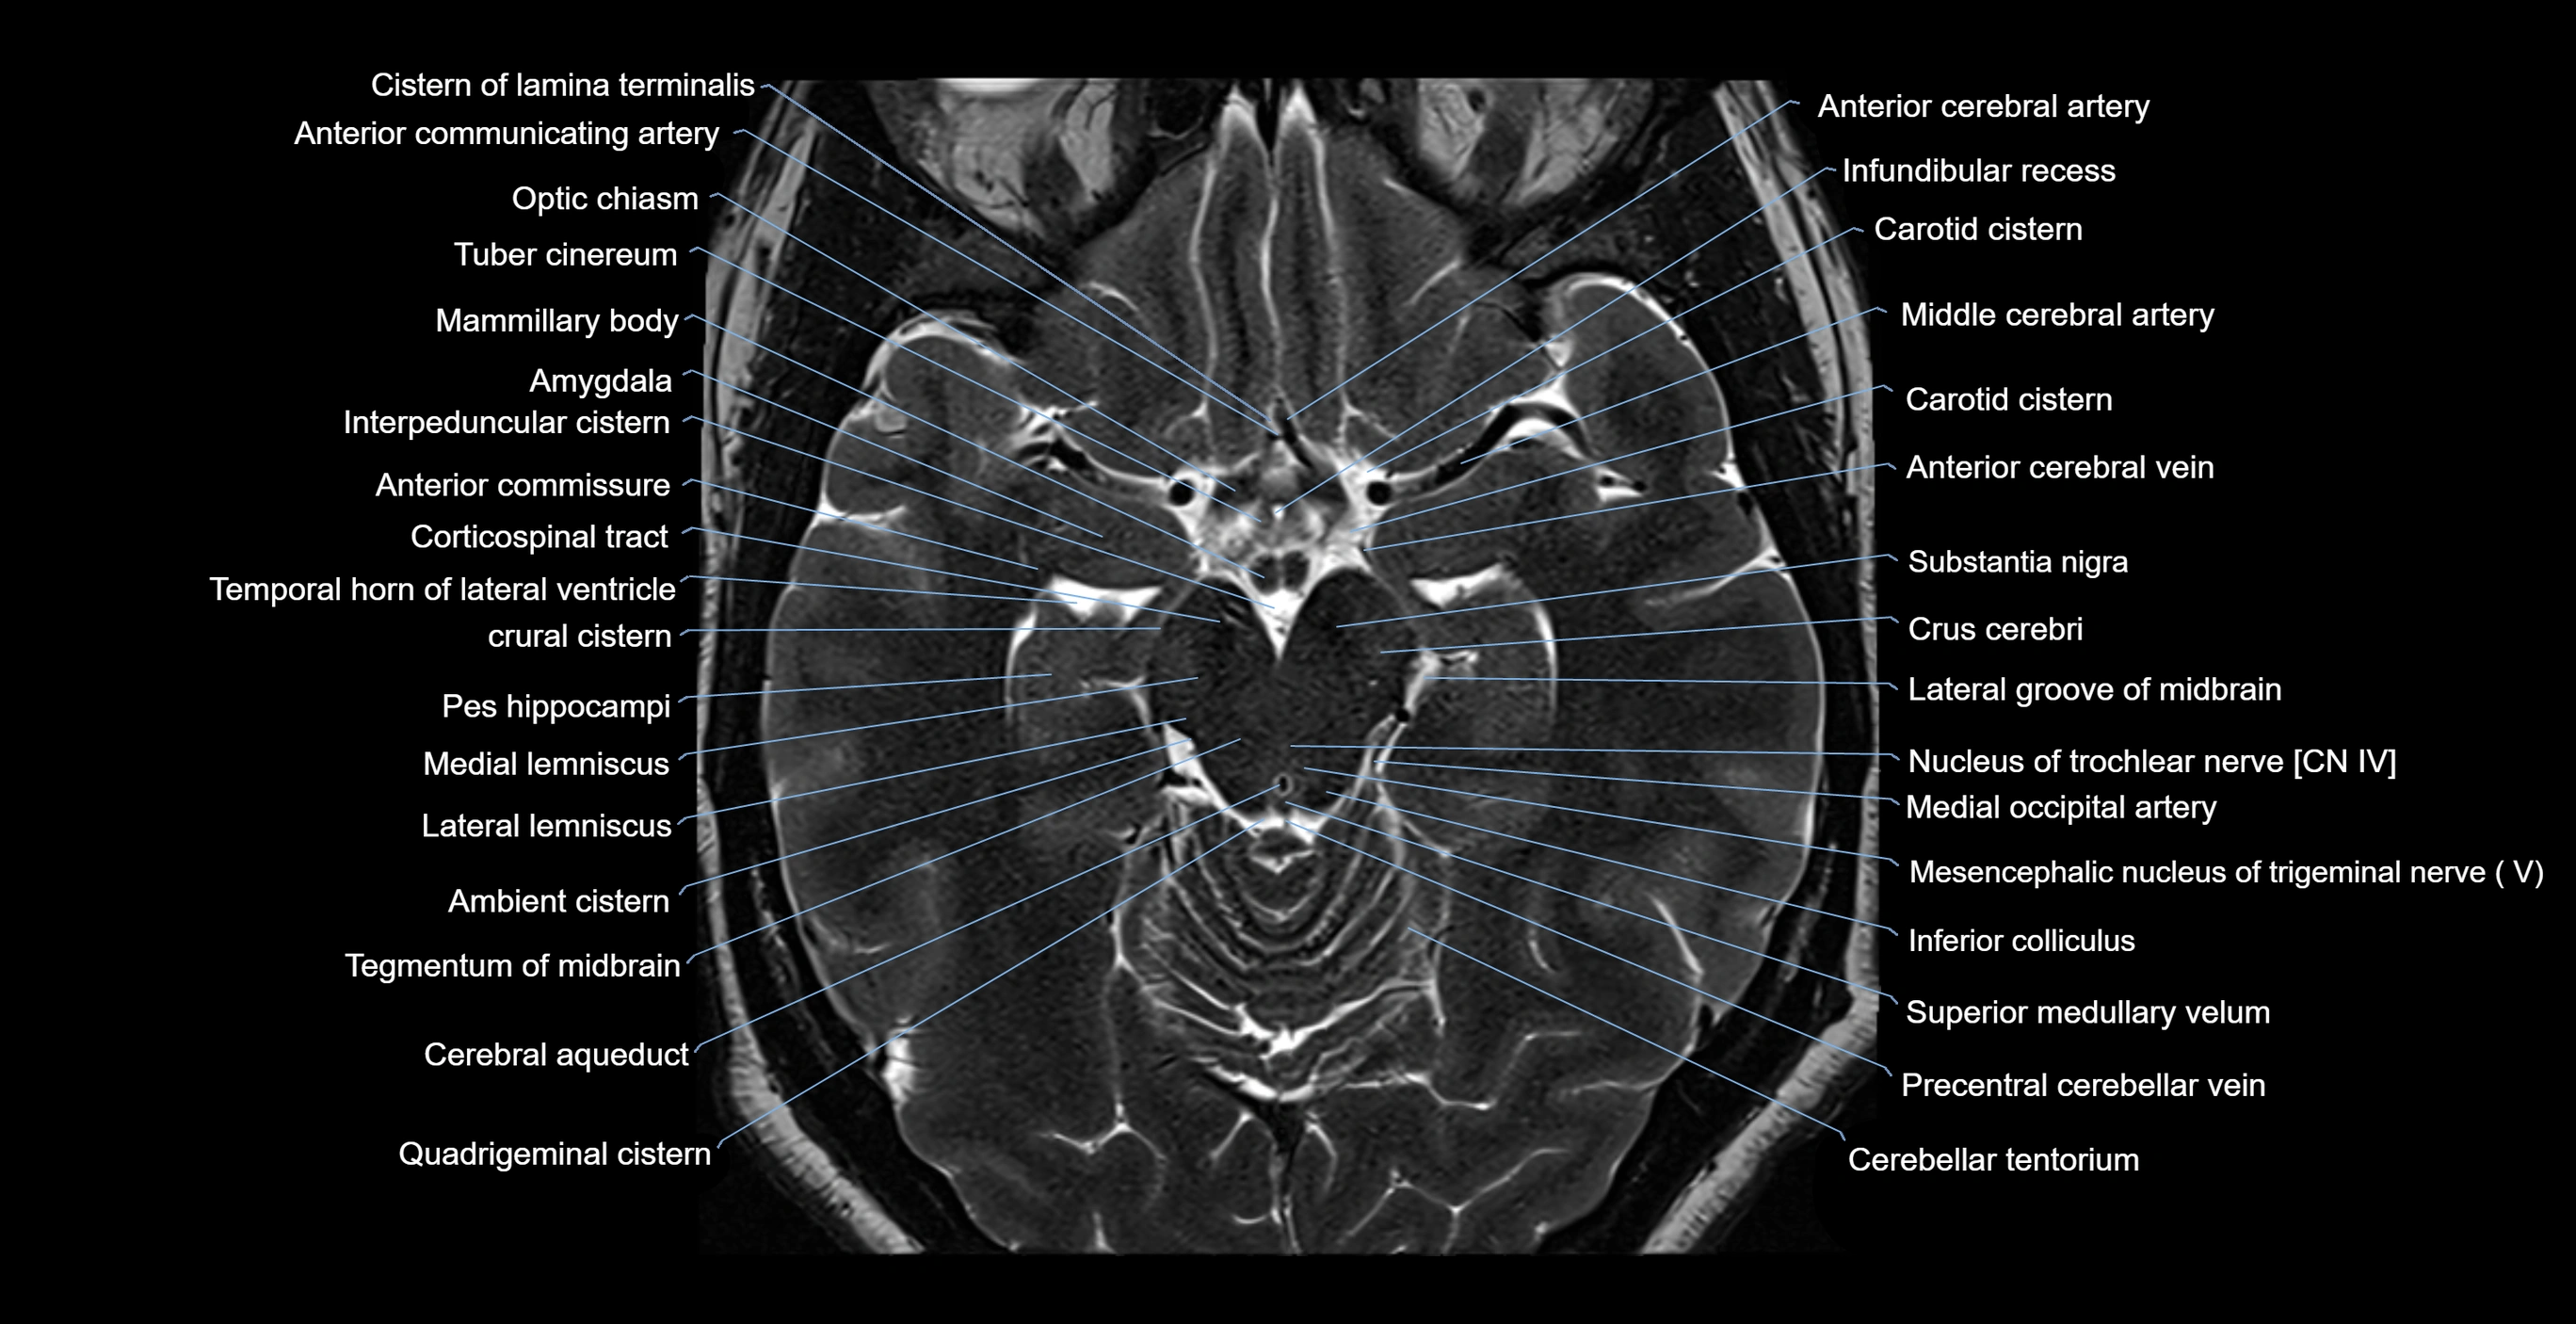

- Ambient cistern

- Amygdala

- Anterior commissure

- Carotid cistern

- Cerebral aqueduct

- Cerebral crus

- Cistern of lamina terminalis

- Crural cistern

- Crus cerebri

- Inferior colliculus

- Infundibular recess

- Interpeduncular Cistern

- Lateral groove of midbrain

- Lateral lemniscus

- Mammillary body

- Medial occipital artery

- Mesencephalic nucleus of trigeminal nerve

- Nucleus of trochlear nerve

- Optic chiasm

- Optic tract

- Pes hippocampi

- Precentral cerebellar vein

- Quadrigeminal cistern

- Substantia nigra

- Superior colliculus

- Superior medullary velum

- Tegmentum of midbrain